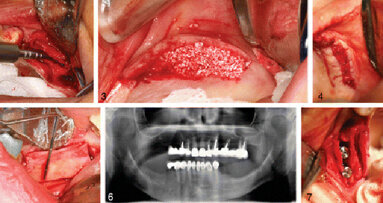

NEW YORK, N.Y., USA: Dental techniques to modify the alveolar ridge have been around for many years, often as a means of support for dentures. As dental ...